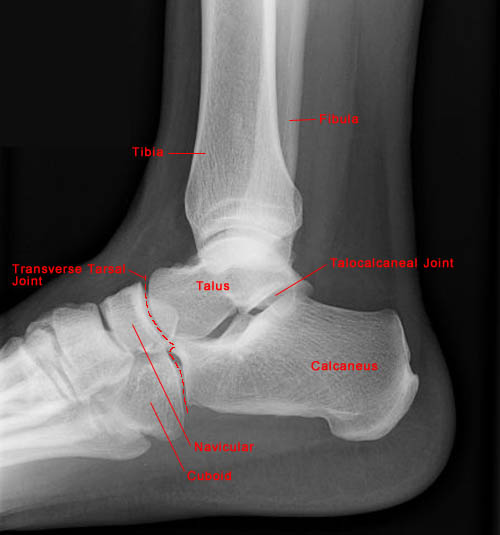

Lateral View of Normal Ankle

• The ankle joint includes articulations between three structures: tibia, fibula and talus.

• The lateral malleolus is longer than the medial malleolus, a characteristic important for joint stability.

• Movement at the ankle joint is limited to dorsiflexion and plantarflexion. However, ankle movement is typically combined with movement of joints in the foot resulting in many ranges of motion.